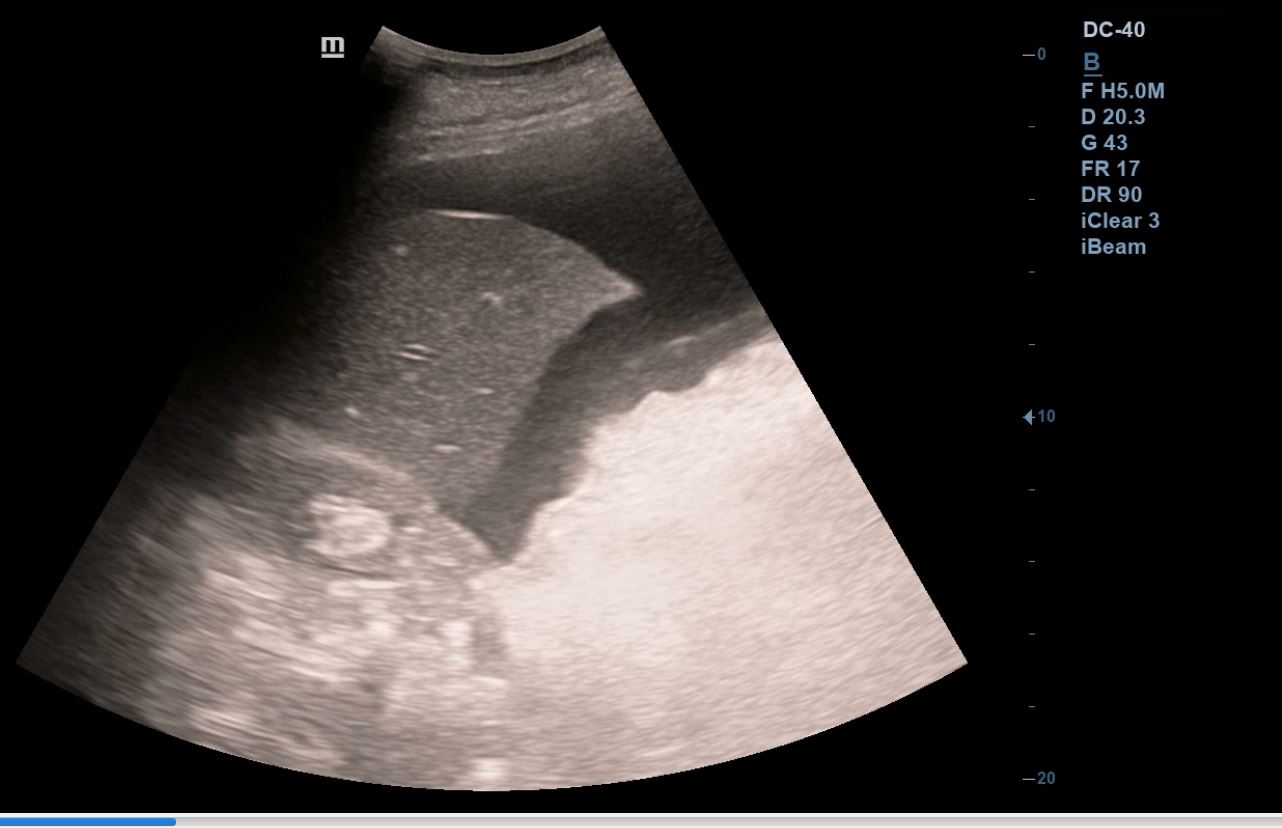

Se realiza ecografía clínica abdominal y pulmonar en la consulta, donde se visualiza líquido libre en espacio hepatorenal, esplenorenal y espacio de Douglas. En región pélvica presenta masa de aspecto heterogéneo con zonas anecoicas de 12 x 10 cm, con mapa color positivo. En la ecografía pulmonar presenta derrame pleural derecho.